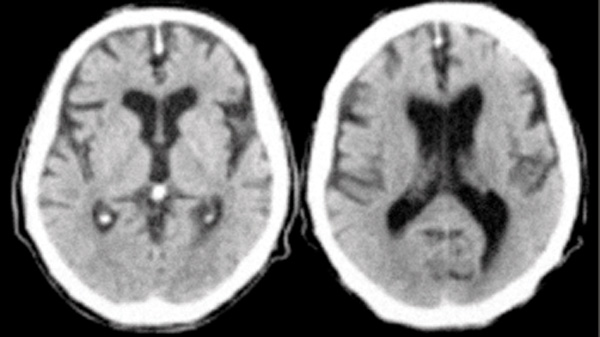

• Marcadores de neuroimagen: son las más utilizadas para el diagnóstico del Alzheimer; y se dividen en técnicas estructurales (Tomografía Axial Computarizada, Resonancia Magnética) y técnicas funcionales (Resonancia Magnética funcional, Tomografía por emisión de positrones).

Figura II. Tomografía axial computada de encéfalo que evidencia una gran atrofia frontotemporal.

En Costa Rica se cree que los afectados pueden oscilar entre los 2700 y los 9000 enfermos. ( 4 ) Pero la mayoría de estos casos no se han diagnosticado ya que esta enfermedad no solo esta acompañada de síntomas de demencia sino también de alteraciones de conductas y lesiones anatomopatológicas

(pérdida de neuronas y atrofia  cerebral de predominio temporo-fronto-parietal).